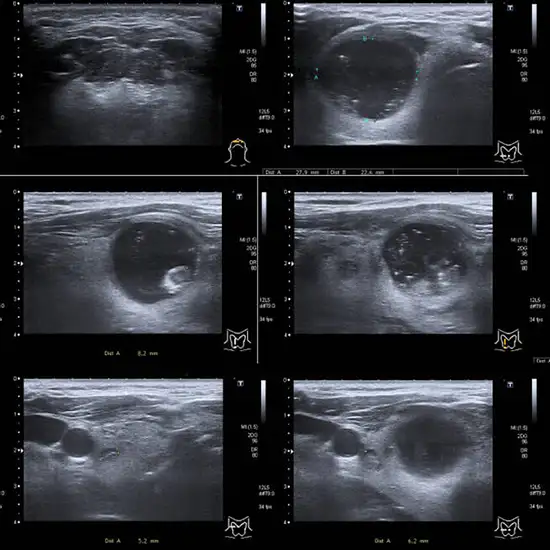

Thyroid ultrasonography is a type of ultrasound that employs sound waves to create images of the thyroid gland in the neck—typically used to look for any lumps or nodules near the neck.

The best way to learn about the shape and structure of nodules is with a thyroid ultrasound. Doctors may use it to distinguish cysts from solid nodules or to determine the presence of multiple nodules. It can also be used as a guide by doctors when performing a fine-needle aspiration biopsy.